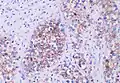

Histopathology of classical seminoma, with typical features.[1] | |

Microscopic examination shows that seminomas are usually composed of either a sheet-like or lobular pattern of cells with a fibrous stromal network. The fibrous septa almost always contain focal lymphocyte inclusions, and granulomas are sometimes seen. The tumour cells themselves typically have abundant clear to pale pink cytoplasm containing abundant glycogen, which is demonstrable with a periodic acid-Schiff (PAS) stain. The nuclei are prominent and usually contain one or two large nucleoli, and have prominent nuclear membranes. Foci of syncytiotrophoblastic cells may be present in varied amounts. The adjacent testicular tissue commonly shows intratubular germ cell neoplasia, and may also show variable spermatocytic maturation arrest.[5]

The germ cell markers OCT 3/4 and CD117 (positive immunohistochemistry pictured) are useful for diagnosis.[10]